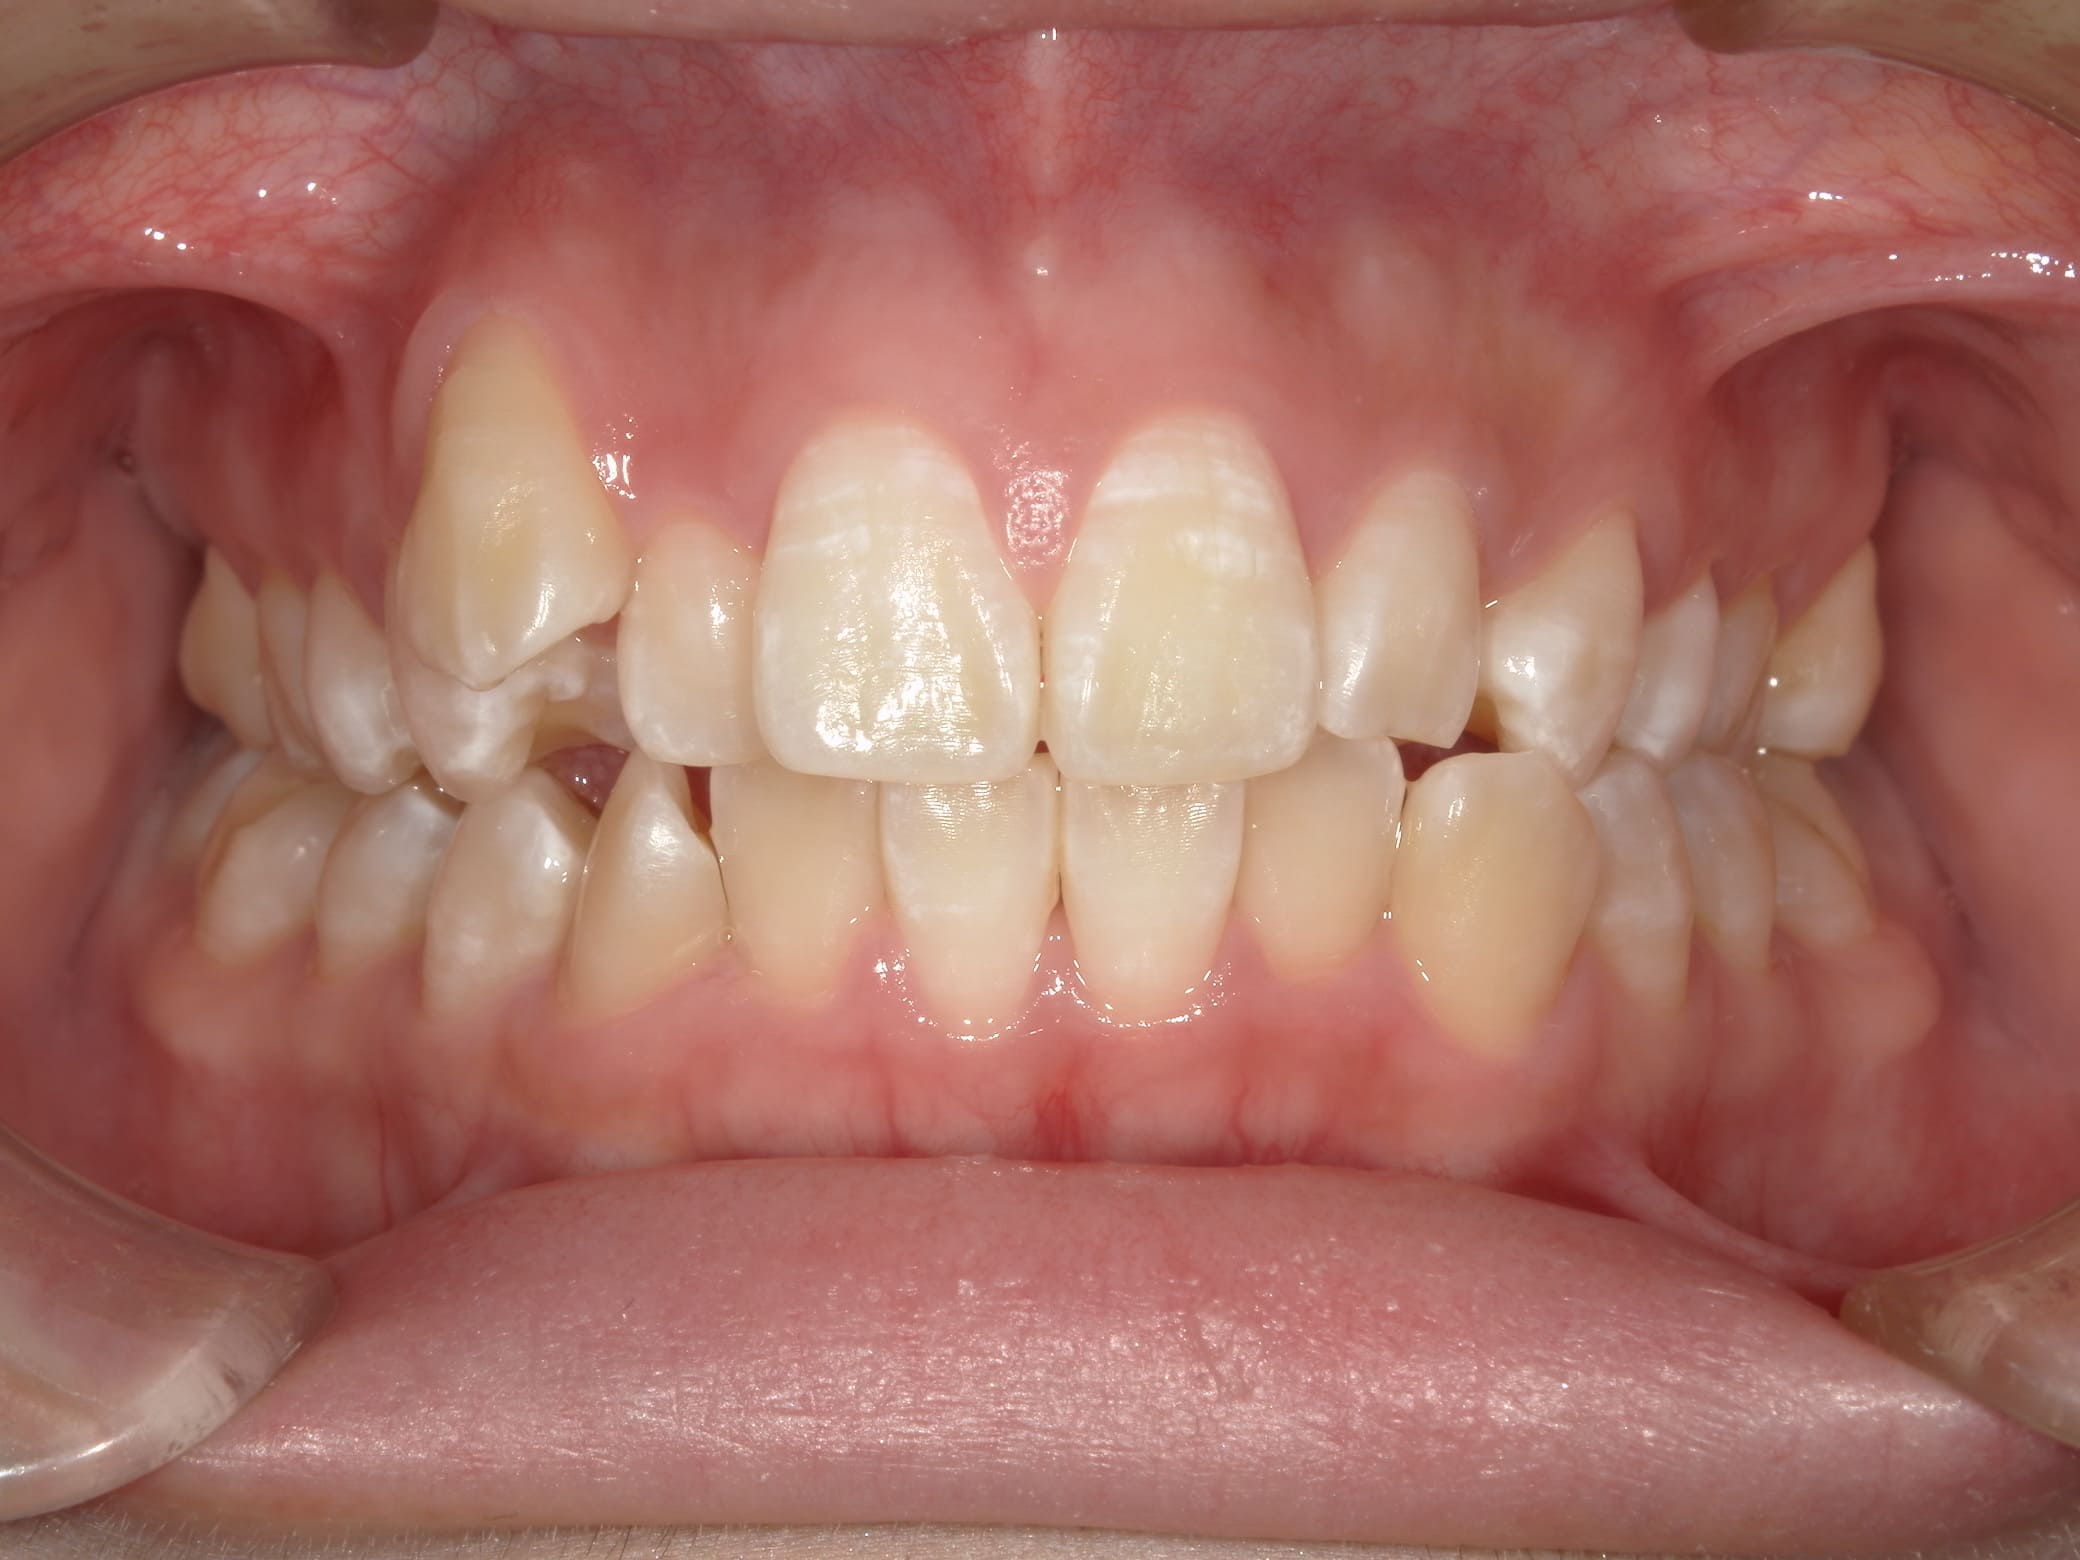

| 年齢・性別 | 21歳 |

|---|---|

| 主訴 | 叢生が気になる・前歯に埋伏歯がある |

| 治療期間・回数 | 6ヶ月 |

| 費用 | 935,000円 |

| 上顎の左側3番が埋伏していたため、上顎左右の3番および親知らずを抜歯し、矯正治療を行いました。 治療開始からおよそ6ヶ月で歯列が整い、審美的にも機能的にも良好な結果が得られた症例です。 |